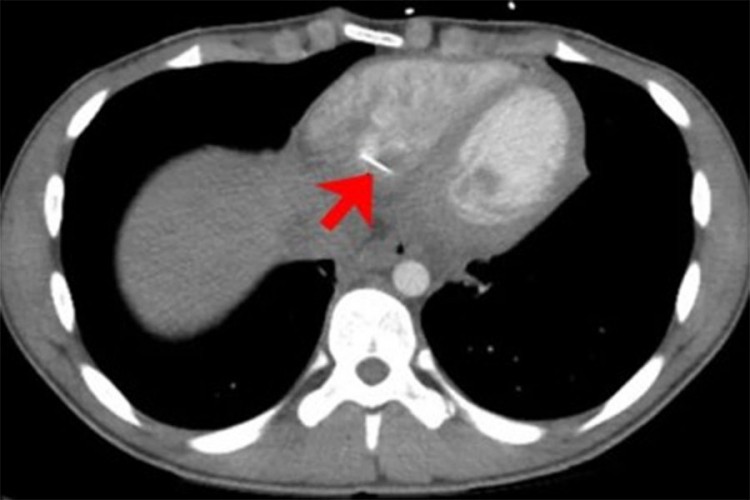

Skeniranjem srca primećen je linearno metalno strane telo u srcu. Predmet je bio oko 3,5 centimetra dugačak i virio je iz donjeg dijela desne komore srca, koja pumpa krv u pluća.